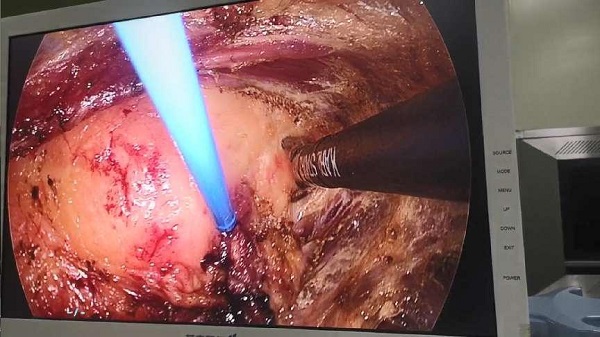

胸大肌内巨大脂肪瘤,腔镜下微创完成手术。